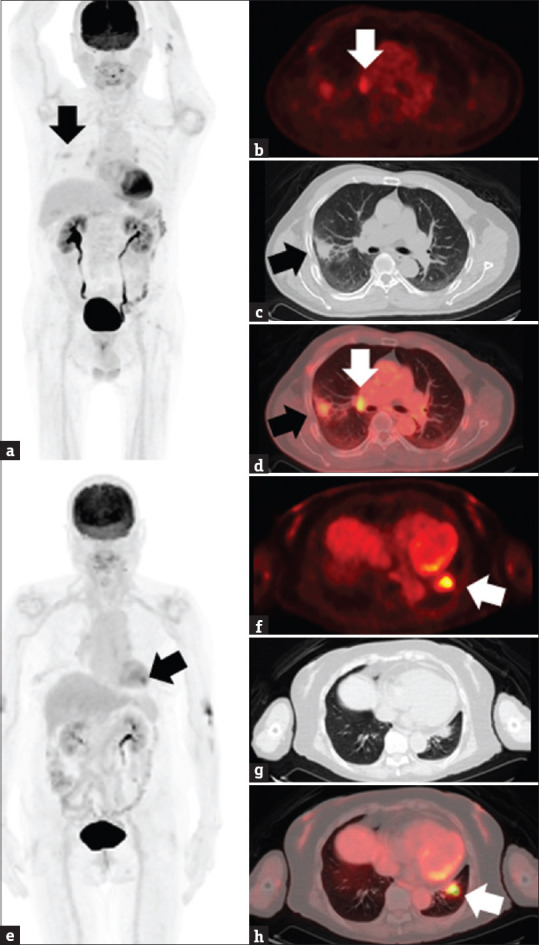

Currently, the second most commonly diagnosed cancer in the world is lung cancer, and 85% of cases are non-small cell lung cancer (NSCLC). With growing knowledge of oncogene drivers and cancer immunology, several novel therapeutics have emerged to improve the prognostic outcomes of NSCLC. However, treatment outcomes remain diverse, and an accurate tool to achieve precision medicine is an unmet need. Radiomics, a method of extracting medical imaging features, is promising for precision medicine. Among all radiomic tools, 18F-fluorodeoxyglucose positron emission tomography (18F-FDG PET)-based radiomics provides distinct information on glycolytic activity and heterogeneity. In this review, we collected relevant literature from PubMed and summarized the various applications of 18F-FDG PET-derived radiomics in improving the detection of metastasis, subtyping histopathologies, characterizing driver mutations, assessing treatment response, and evaluating survival outcomes of NSCLC. Furthermore, we reviewed the values of 18F-FDG PET-based deep learning. Finally, several challenges and caveats exist in the implementation of 18F-FDG PET-based radiomics for NSCLC. Implementing 18F-FDG PET-based radiomics in clinical practice is necessary to ensure reproducibility. Moreover, basic studies elucidating the underlying biological significance of 18F-FDG PET-based radiomics are lacking. Current inadequacies hamper immediate clinical adoption; however, radiomic studies are progressively addressing these issues. 18F-FDG PET-based radiomics remains an invaluable and indispensable aspect of precision medicine for NSCLC.